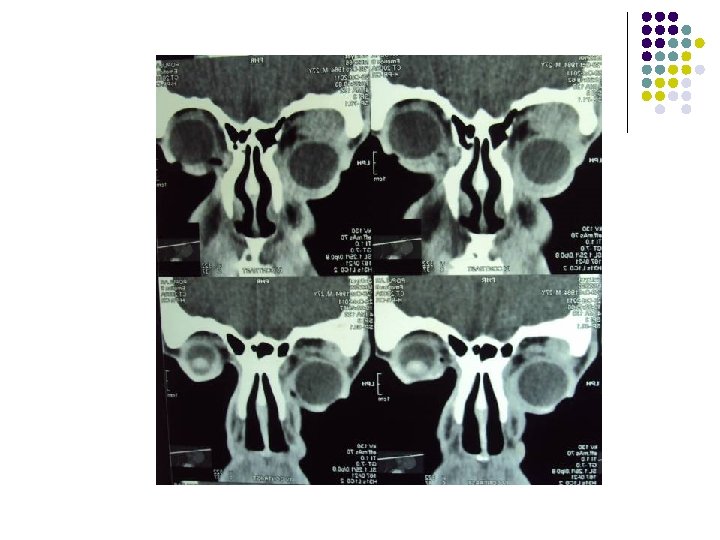

CT Scan of Brain

Clinical Diagnosis Retrobulbar solid tumour on left orbit